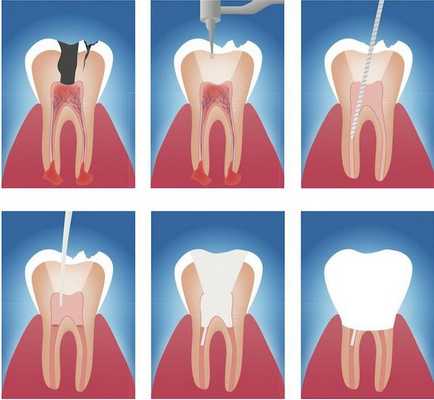

Этапы эндодонтического лечения:

- адекватное обезболивание;

- изоляция зуба или нескольких зубов, в которых будут проводится манипуляции, от полости рта;

- создание эндодонтического доступа (иссечение твёрдых тканей зуба или пломбировочного материала, закрывающих доступ в систему корневого канала;

- прохождение и определение длинны корневого канала (это длинна от устья до верхушки корня);

- создание корневого канала определённого диаметра и формы;

- введение в корневой канал лекарственных препаратов;

- пломбирование корневого канала;

- восстановление анатомии и функции зуба с помощью пломбировочного материала или ортопедической конструкции.